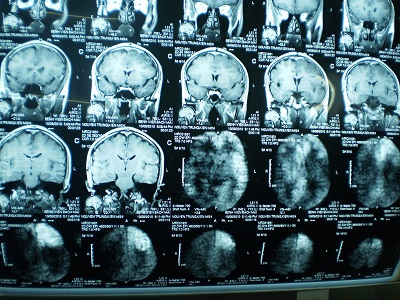

Hình ảnh học

Thực hiện đầu tiên khi nghi ngờ viêm não.

Cung cấp thông tin đánh giá nhiễm trùng hệ thần kinh TW nhưng thường không đặc hiệu. Phát hiện sau khởi phát triệu chứng 2-4 ngày.

MRI nhạy hơn CT trong việc phát hiện sớm những sang thương trên não do HSE (Neurologist 2000;6:145–59.)

Tổn thương gợi ý chẩn đoán: T1 giảm và T2 tăng ở chất xám thuỳ thái dương trong và thuỳ trán ổ mắt, có thể có xuất huyết kèm theo, thường không đối xứng. Ngoài ra tổn thương có thể lan đến thuỳ đảo và hồi góc, có thể bắt Gado màng não và các hồi não.

MRI bình thường trong khoảng 10% BN HSV-PCR (+). Nhưng số còn lại đều có tổn thương thuỳ thái dương (90%)